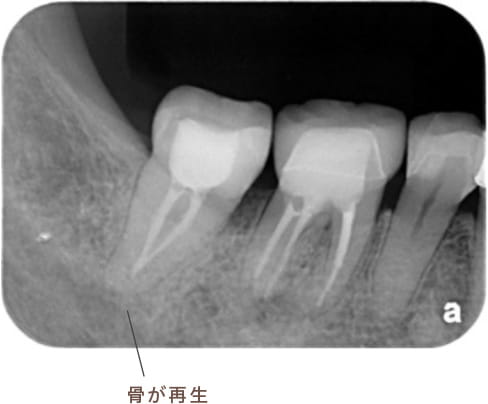

治療後病気がなくなり骨が再生した

細菌の栄養源が絶たれ、膿が消えて骨が再生し、歯を元のように使い続けることができます。